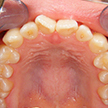

2. 術前上顎

上顎面観でやはり1,1番の翼状捻転および3,3番の捻転が著名。2次成長期を迎える患者様において、上顎歯列弓は劣成長と思われます。